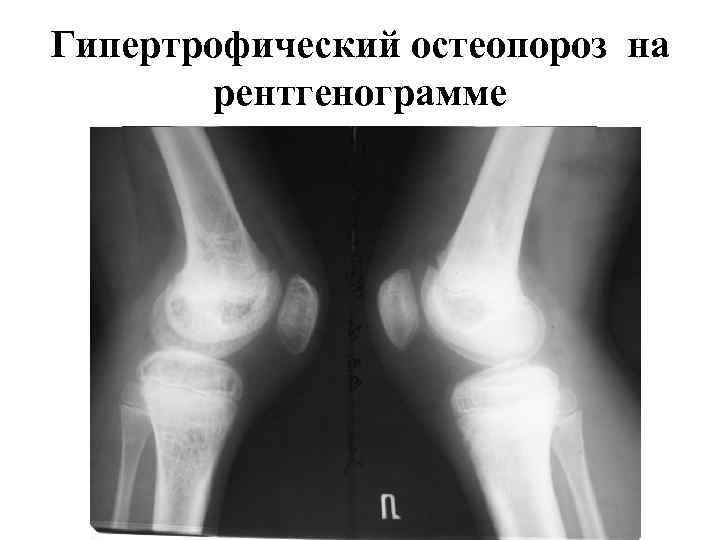

Гипертрофический остеопороз на рентгенограмме